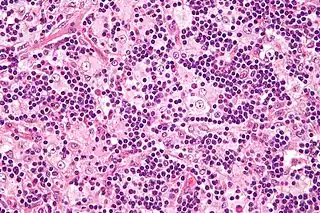

![]() Micrografía de un nodo linfático afectado por la enfermedad de Rosai-Dorfman mostrando emperipolesis. Tinción H&E. | ||

La enfermedad de Rosai–Dorfman, también conocida como Histiocitosis sinusoidal es una rara enfermedad benigna de causa desconocida que se caracteriza por la sobreproducción de histiocitos, los cuales se acumulan en los ganglios linfáticos a través de todo el cuerpo.[1] Las linfoadenopatías del cuello son el lugar más característico para la acumulación de histiocitos, aunque la acumulación también puede ser extraganglionar. La piel, el tracto respiratorio alto y las cavidades sinusales son los lugares extraganglionares que con mayor frecuencia se ven afectados.[2][3] Los síntomas de la enfermedad pueden variar según el lugar que se vea comprometido. El nombre proviene de Ronald F. Dorfman y Juan Rosai.